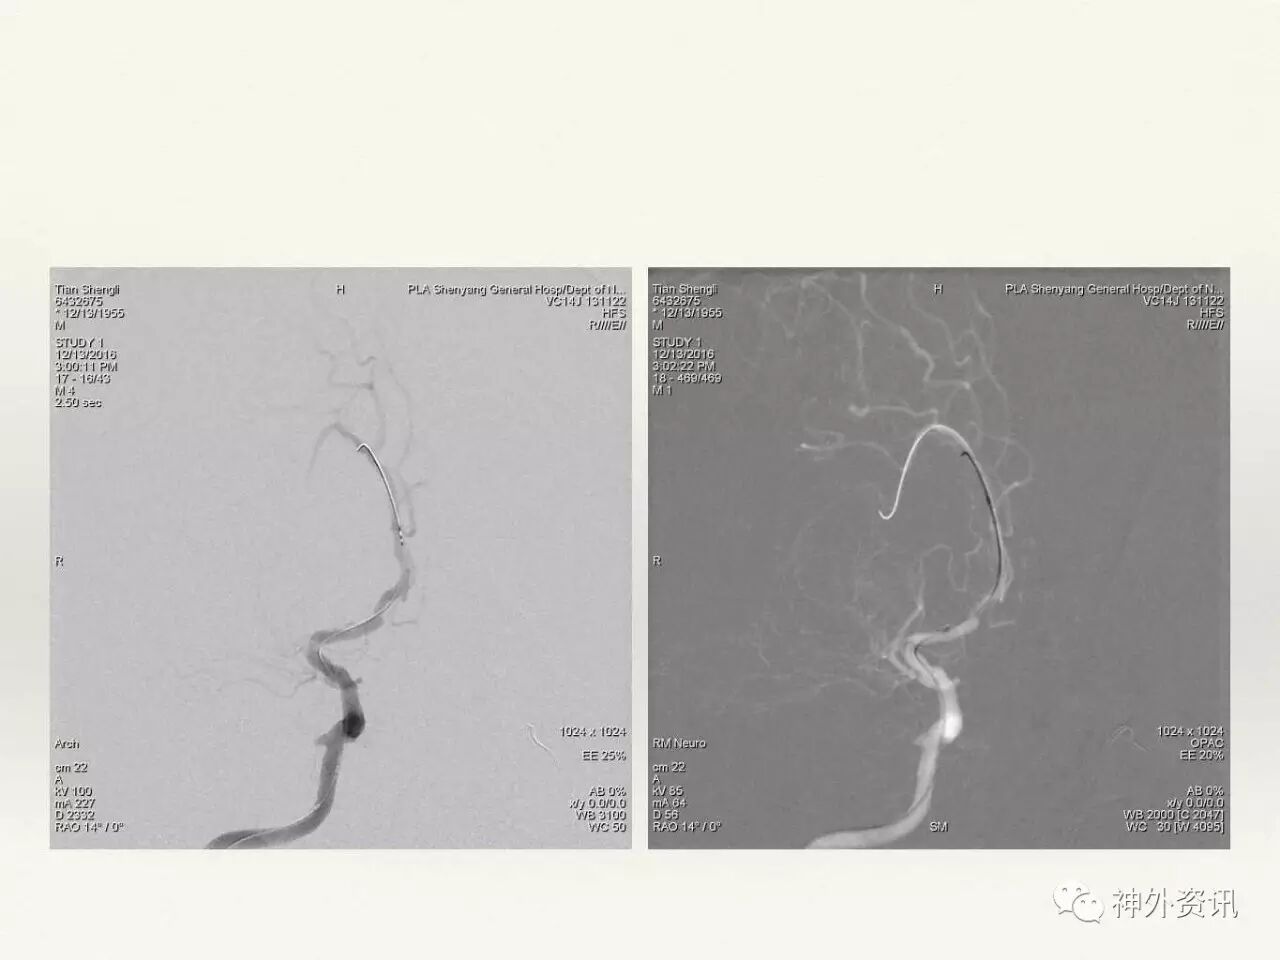

在东北地区率先开展了颈内动脉、大脑中动脉及基底动脉闭塞血管内再通、颅内动脉栓塞急性期取栓、血流导向装置治疗大型宽颈动脉瘤等,对颅内动脉瘤、动静脉畸形、颈动脉及颅内动脉狭窄、颈内动脉海绵窦瘘、硬脑膜动静脉瘘等外科治疗具有较深的造诣。完成脑血管造影8600余例,各类脑血管病介入手术共4500余例,动脉瘤、动静脉畸形、脑肿瘤、脑出血及脑外伤等外科手术1500余例。